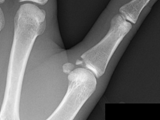

Gamekeepers thumb

Gamekeepers thumb